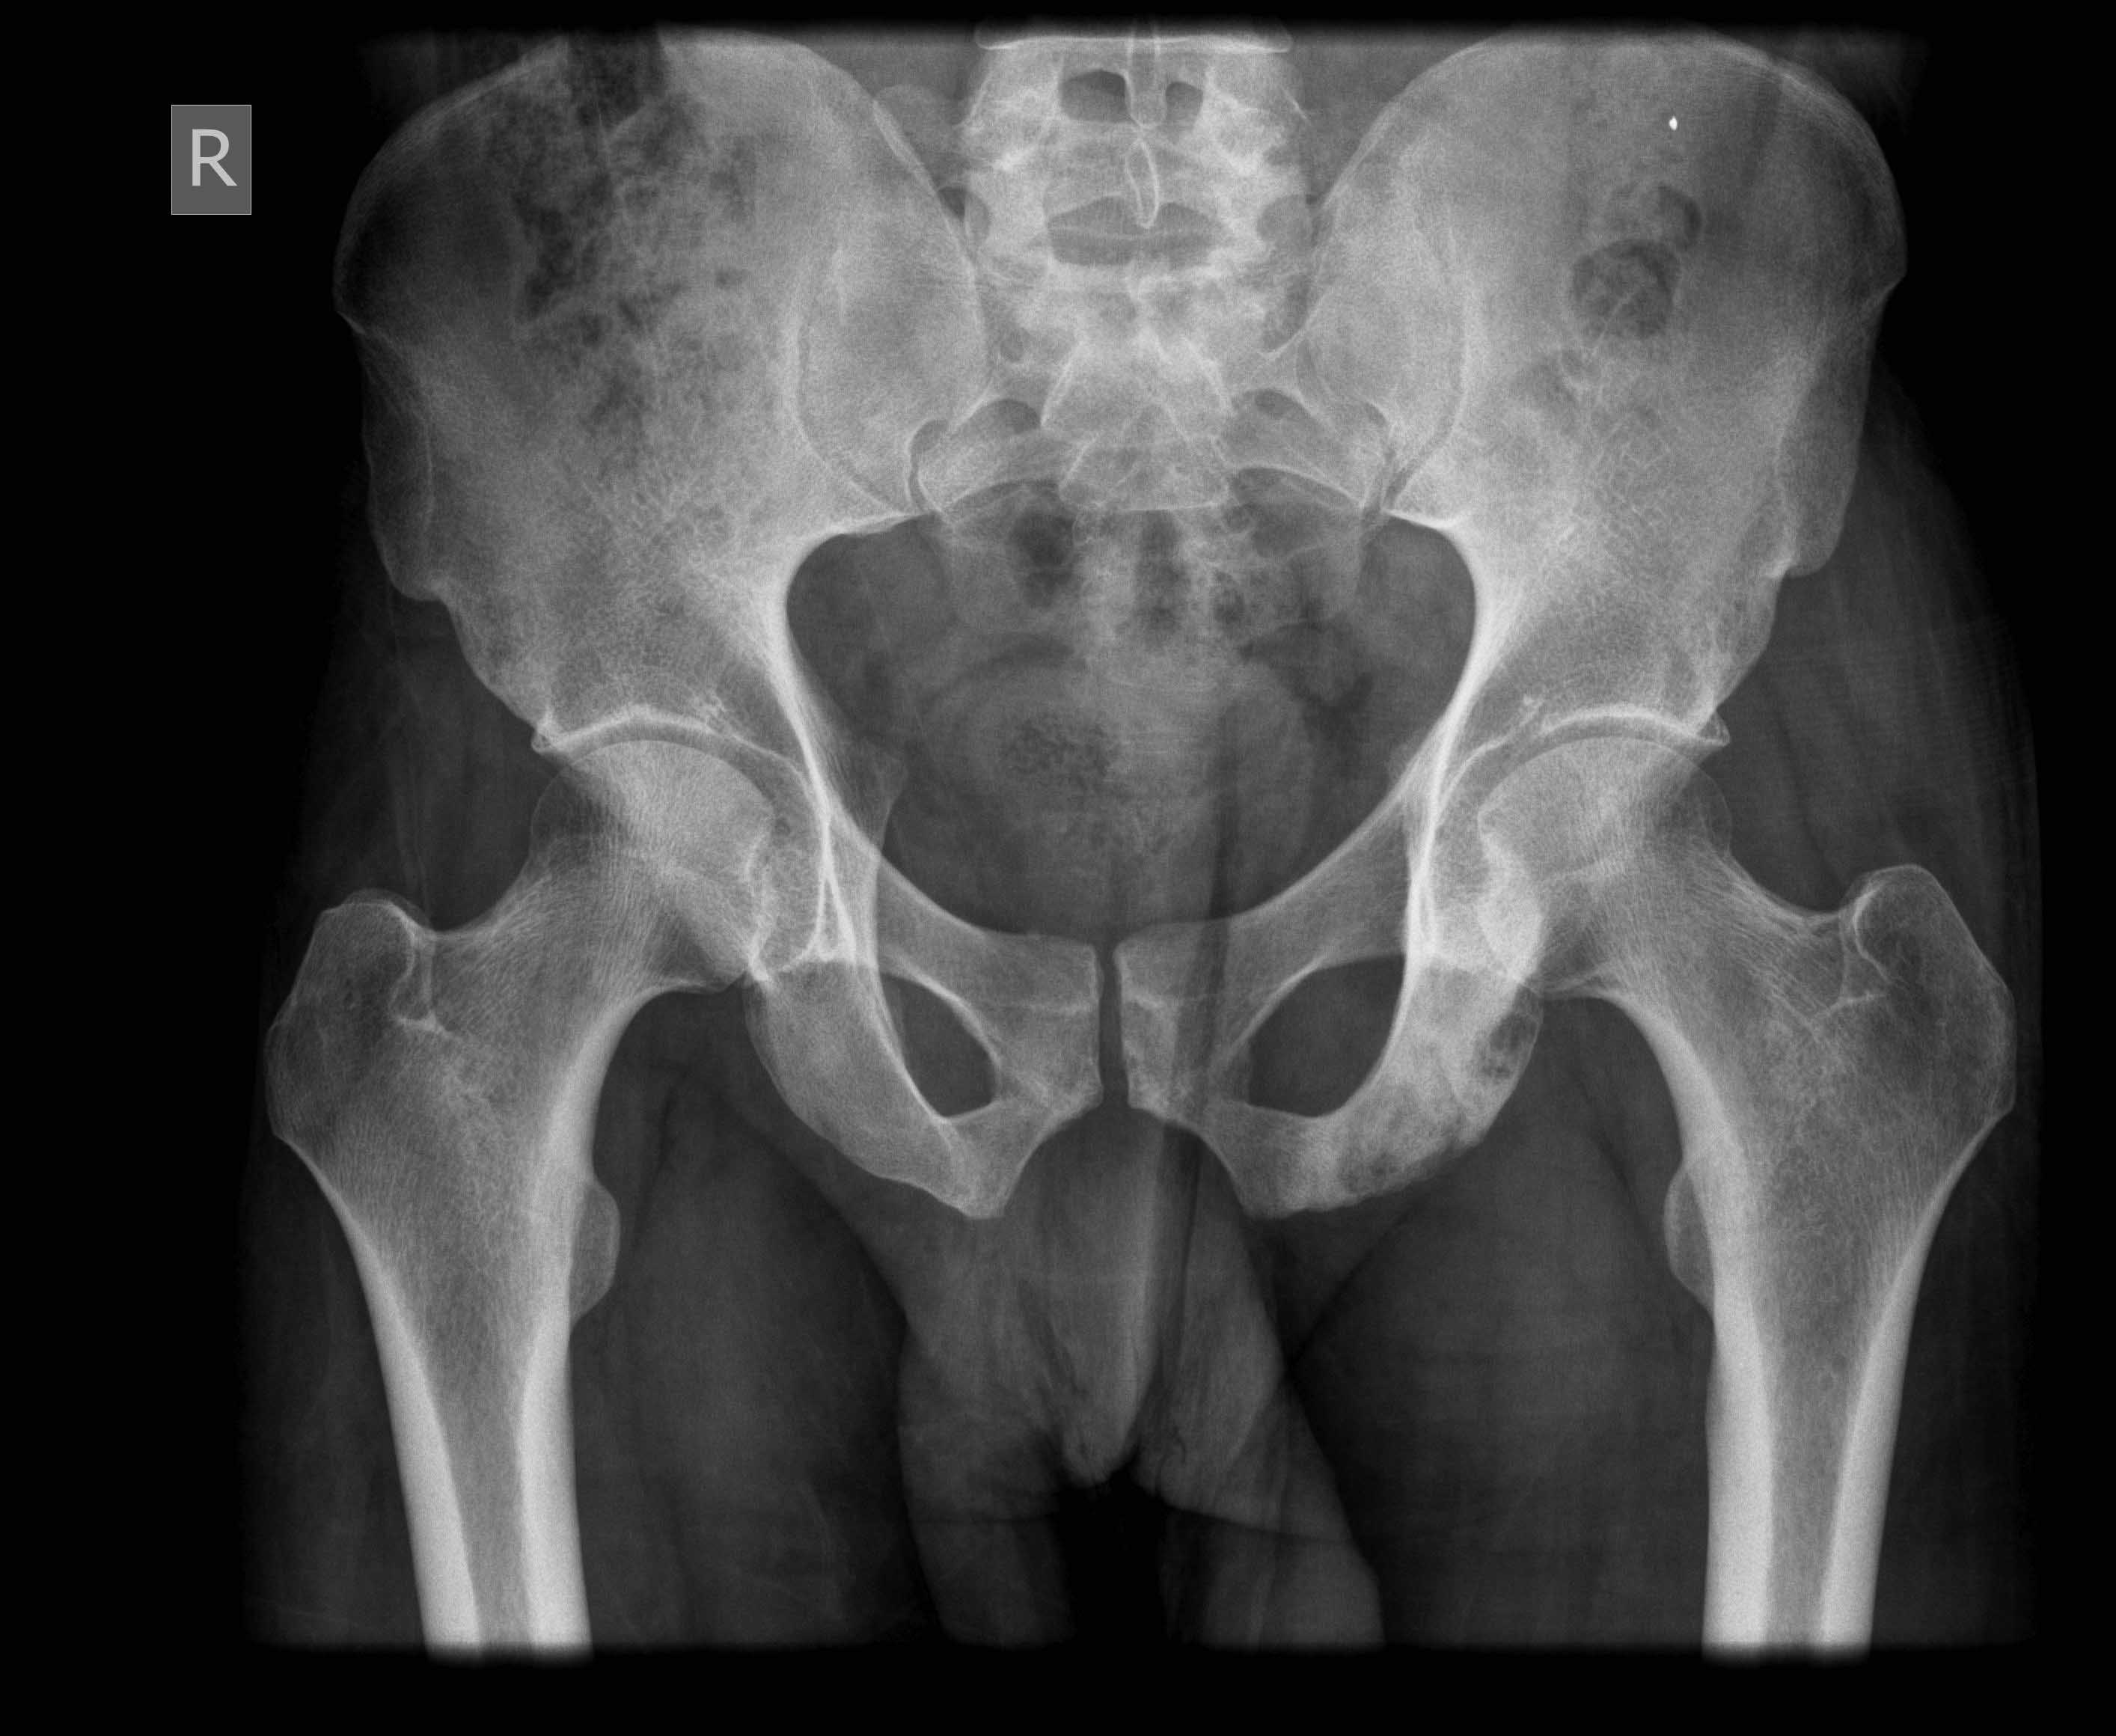

Найден снимок 4-х месячной давности,

left pubic ramus pagetoid

Наиболее вероятны очаги туб. остита в своде левой вертлужной впадины и в левой седалищной кости.

Рентгенолог УНИИТО Зельский И.А.

Слева седалищная кость подозрительная. Еще интересно взглянуть на рентген поясничного отдела.